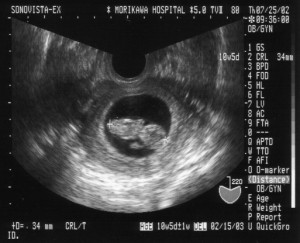

エコー検査で週数を決める場合

だいたいの目安として胎嚢(胎児の入っている袋)が経腟エコーで見えてくるのが妊娠5週くらい、卵黄嚢(york sacという)という丸い構造物が見えてくるのが6週くらい、胎児の心拍が見えてくるのが7週くらい、胎児が1cmになるのが8週くらい、その後は胎児の長さに7を足した程度が妊娠のだいたいの週数と言われています。最近は超音波の機械がしっかりしたグラフを元に計算してくれるのでもっとちゃんと週数がはじき出されますが、おおむねそれくらいと考えて差し支えありません。

しかしこのような計算ができるのは妊娠の12週くらいまででそれ以降は胎児の個人差により発育の速度が変わってきますので、大きさから週数を割り出すのはできにくくなります。特にお産後授乳している人がまだ生理もしっかりないのに妊娠したりすると妊娠週数はエコーを見なければ全くわかりません、それも妊娠の早くに来てもらえればいいのですが、かなり進んでからこられるともはや妊娠週数不明のまま見ていくしかありません。